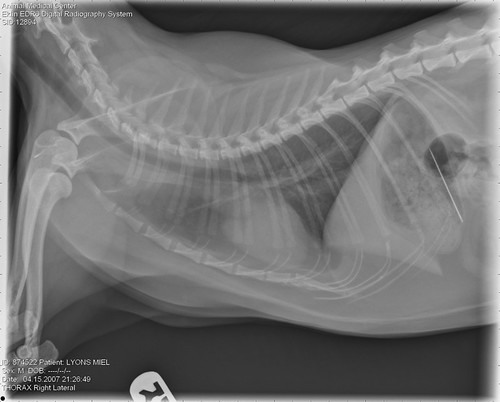

CHANNEL YOUTUBE : VetCT - Teleradiology | Teleconsulting | Education